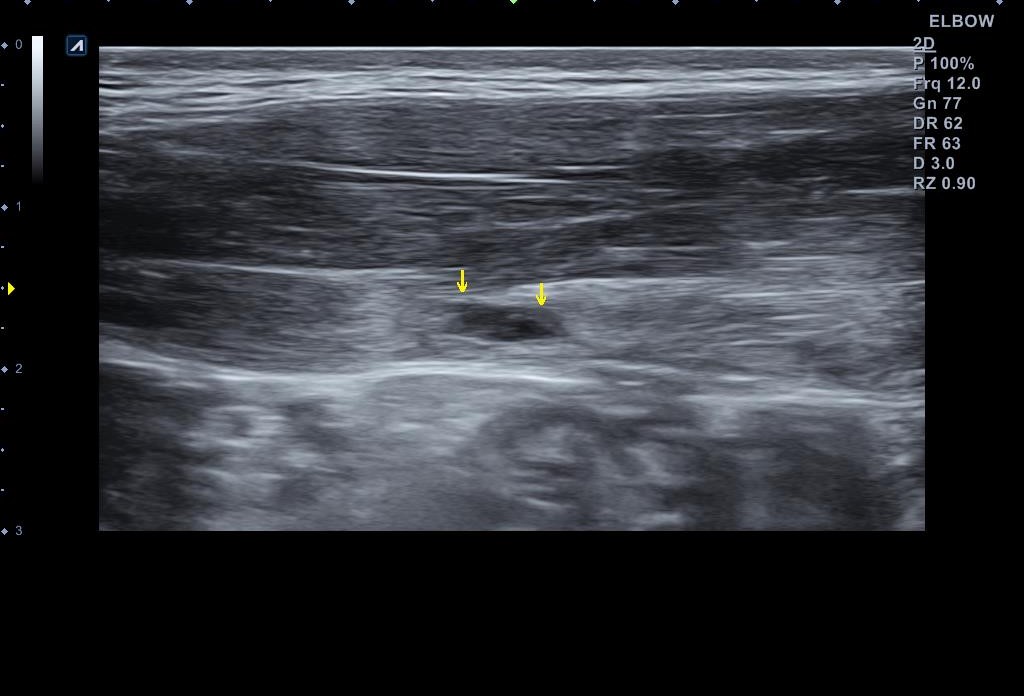

왜 슬픈 예감은 틀린적이 없을까요...일주일만에 다시 시행한 초음파 검사 상에서는... 복직근 파열이 훨씬 심해져 있었습니다.

나 : 초음파 한번 보세요.... 지난주에 비해 파열 크기가 훨씬 커졌어요... 근육에 빵꾸가 2개나 나버렸어요...